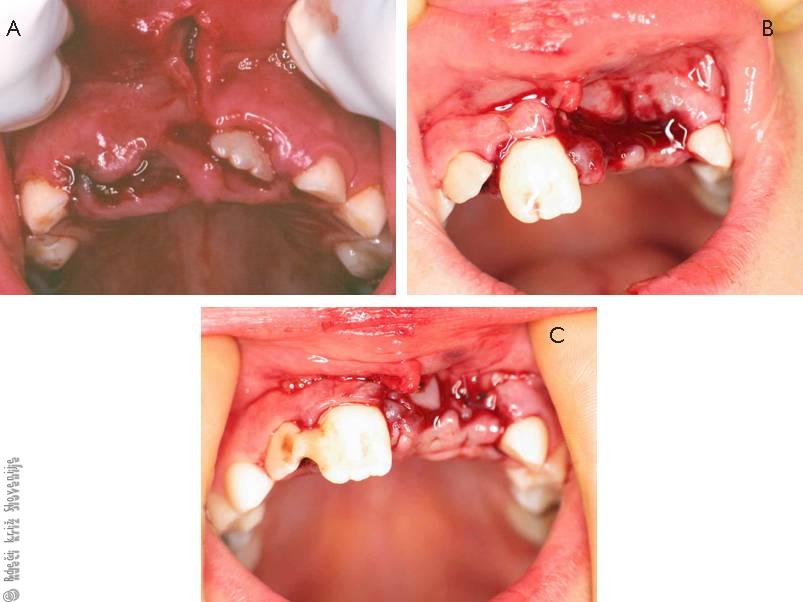

Slika 8

A – Pri padcu na rob mize je pri 7-letnem otroku prišlo do vtisnjenja obeh srednjih zgornjih sekalcev v kost (intrusio). Desnega sekalca pod otečeno in raztgano dlesnijo ni mogoče videti in ob površnem pregledu bi lahko sklepali, da gre za izbitje zoba.

B – Devetletni otrok si je pri padcu na gozdni poti izbil oba leva zgornja sekalca, ki jih na mestu poškodbe niso našli. Desni srednji sekalec je premaknjen iz zobnice (ekstruzija). Vidna je razpočna rana dlesni.

C – Desni srednji sekalec je naravnan in začasno imobiliziran ob sosednji zob. Oskrbljena je mehkotkivna poškodba v predelu izbitih zob levo.